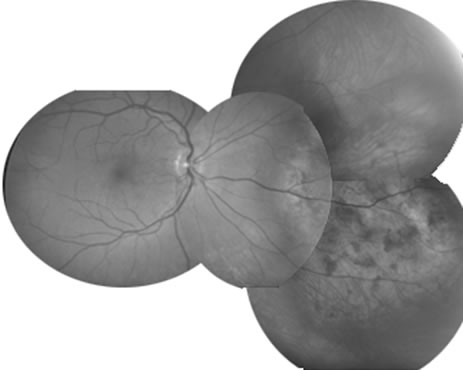

A number of adult cardiovascular diseases can produce ophthalmic manifestations that simulate uveitis. In severe hypertension, retinal detachment, small choroidal vascular insults, cotton wool spots, and hemorrhages may occur, simulating posterior uveitis (Fig. 23). In patients with carotid artery disease, anterior segment ischemia similar to mild anterior uveitis may be observed. This pattern may also occur after either extensive ocular irradiation or disinsertion of more than two extraocular muscles during retinal or strabismus surgery.

Fig. 23. Atypical severe hypertension with exudative detachment and choroidal lesions.